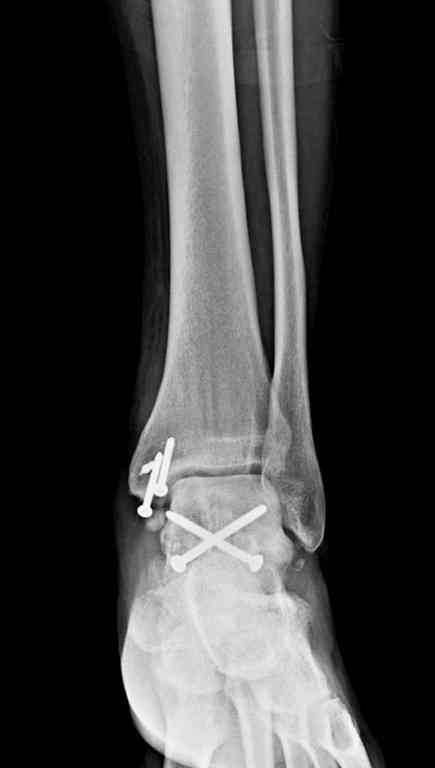

Здесь на фото примеры:

Переломовывих тарана с повреждением медиальной стороны. Через 4 часа после поступления проведена репозиция и фиксация тарана после Irrigation&Debridment. Частичное несращение медиальной лодыжки не беспокоит, вернулся к активному образу жизни. Полная нагрузка разрешена через 11 недель. Финальные снимки через 11 месяцев.

Второй случай прооперирован вчера.

10 дней назад поступил с открытым повреждением медиальной лодыжки и переломо вывихом таранной кости. Ургентно сделана репозиция с наложением наружного фиксатора + Irrigation&Debridment.

Вчера провели фиксацию.

Из-за многооскольчатости дистальной части малоберцовой, где невозможно было провести фиксацию шурупами, перелом зафиксирован подпирающей пластиной, которая должна служить дополнением отсутствующей дистальной части малоберцовой (lateral cortex substitute).

Для стабильности два шурупа на синдесмоз.

Медиальную рану с приближенными краями продолжаем вакуумировать (KCI). Наружный фиксатор оставлен на пару недель, надеюсь, небольшая рана будет гранулировать и закроется без кожной пластики. Фиксация медиальной ложыжки не планируется.